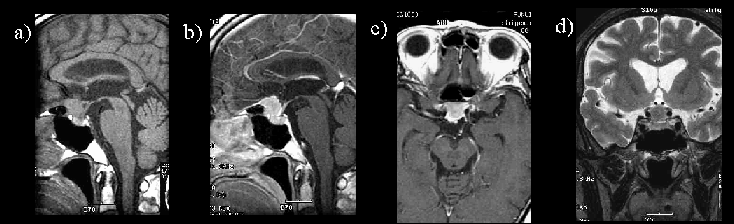

図2 髄膜腫のMRI a)T1強調画像 b)造影後T1強調画像(矢状断) c)造影後T1強調画像(軸位断) d)T2強調画像(冠状断)

鞍内から鞍上部前方にかけて、均一に造影される腫瘤を認める。MRI T1強調画像では、脳実質と等信号で、T2強調画像では、比較的高信号を示している。造影後T1強調画像(矢状断)では、腫瘤の前縁より前頭蓋底の硬膜が染まっている。また腫瘍と下垂体茎の間に視神経交差が描出されている。